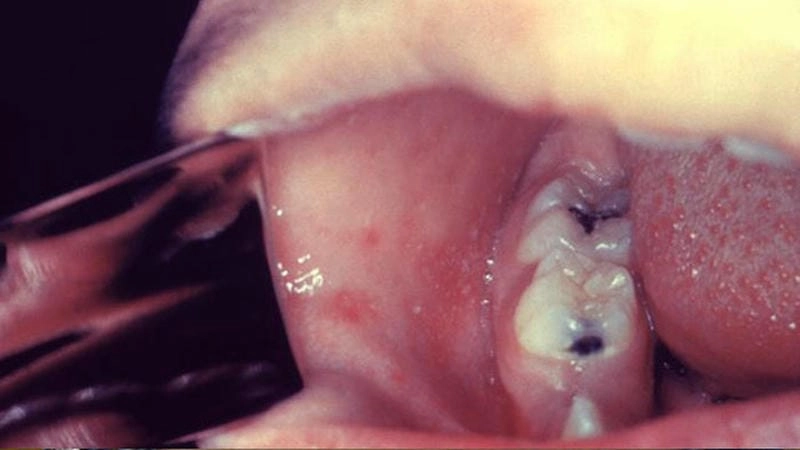

Chỉ cần nhìn một lần hình ảnh về bệnh sởi cũng đủ khiến bạn rùng mình! Những mảng da nổi ban đỏ chi chít, lan rộng từ mặt xuống toàn thân chính là dấu hiệu đặc trưng không thể nhầm lẫn. Dưới ống kính phóng to, từng nốt phát ban lộ rõ như một bản đồ hiểm họa đang dần bộc phát trên cơ thể. Đừng xem thường những dấu hiệu ban đầu – vì đằng sau đó có thể là biến chứng khôn lường nếu không kịp thời phát hiện.

Bạn sẽ choáng váng trước tổng hợp ảnh về bệnh sởi dưới đây – loạt hình ảnh chân thực đến rợn người ghi lại quá trình phát bệnh ở người lớn lẫn trẻ nhỏ. Từ những nốt sẩn đỏ đầu tiên, các vùng da bị bao phủ bởi cơn "bão ban", cho đến khoảnh khắc bệnh nhân vật vã giữa cơn sốt cao và mệt mỏi. Hình ảnh không chỉ nói lên mức độ nghiêm trọng của bệnh mà còn cảnh báo mạnh mẽ về sự lây lan nhanh chóng nếu không kiểm soát tốt.